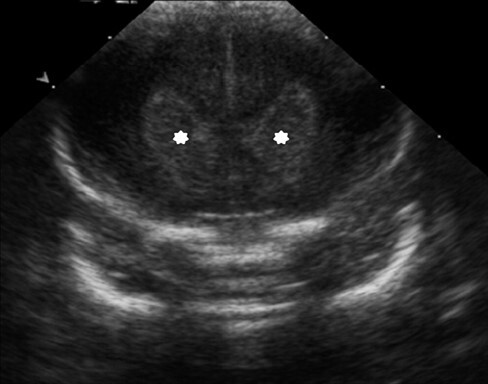

Neonatology Basal Ganglia Hyper-Echogenicity Image